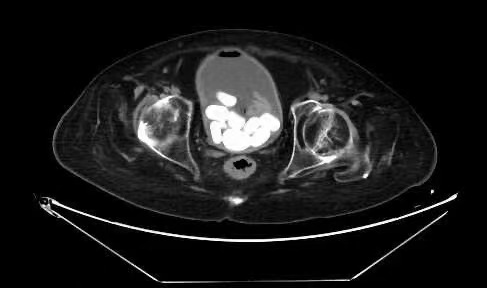

46岁的患者汪某因血尿3天就诊于亚星手机版官方登录泌尿外科。结合CT检查,汪某被确诊为膀胱多发结石。

由于汪某的膀胱结石过多,且既往病史复杂,药物及体外震波碎石无效,与家属充分沟通并取得同意后,泌尿外科主任胡卫东、副主任李伟伟带领团队对汪某实施了局部麻醉下膀胱切开取石术。医生们轻柔仔细地从汪某的膀胱内取出了16块椭圆形扁平状的黄褐色结石,最大的直径达3cm。